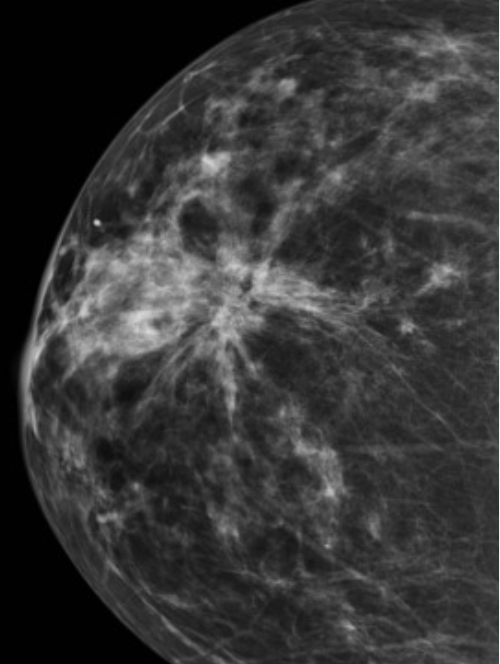

What is a radial scar?

What is the apearance on mammogrphy and histological findings?

Benign sclerosing lesion – central scarring surrounded by proliferating glandular tissue in stellate pattern

• Usually presents as a stellate mass on mammography, closely mimicking carcinoma

• Lesions >1 cm are sometimes called “complex sclerosing lesions”

• Histology – central, fibrous, stellate area [BUZZWORDS]